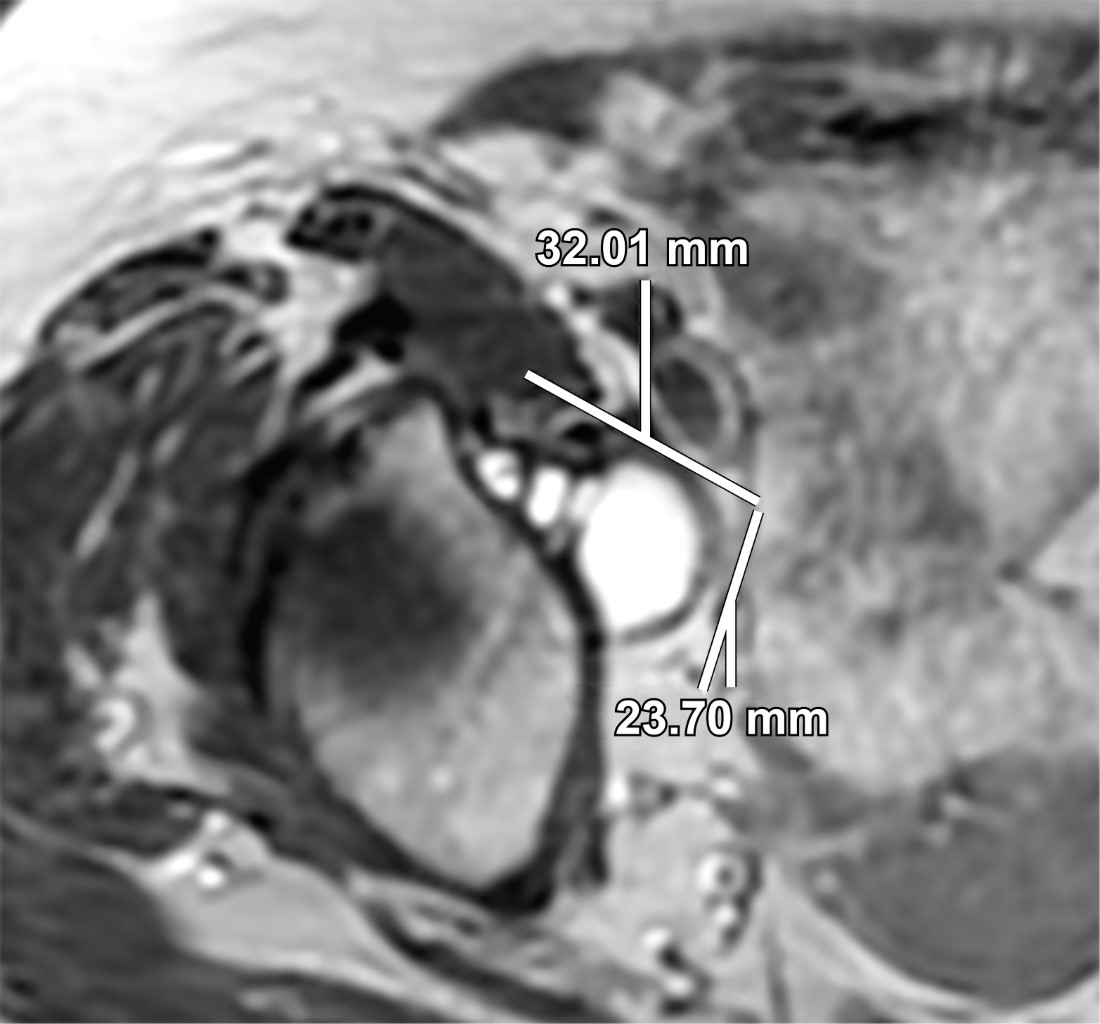

Se le realizó estudio de resonancia magnética de cadera derecha en secuencias potenciadas en T1, T2 y saturación grasa en los planos coronal, sagital y axial. Se observó fractura del labrum acetabular derecho con imagen sacular, de aspecto pediculado multilobulado, de contenido líquido, mide en el plano sagital de 42 × 15 mm, así como imagen circular bien delimitada que continúa hacia la porción superior y por debajo del músculo psoas, con diámetros en el plano sagital de 28 × 22 mm (Figura 1), en el plano coronal mide 32 × 27 cm (Figura 2) y en el axial 32 × 23 mm (Figura 3), sugestiva de quiste paralabral. Signos discretos de coxartrosis bilateral e hipotrofia de los músculos de la región glútea del lado derecho en comparación con el lado izquierdo.

Figura 2